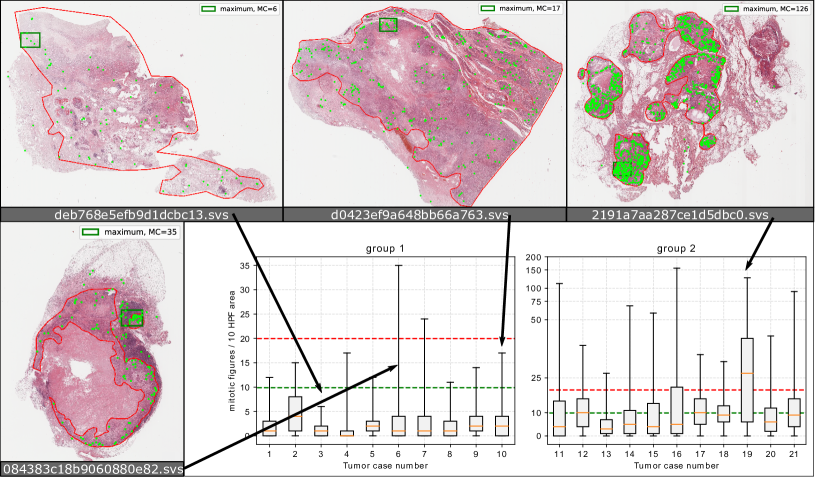

We also investigated the count of mitotic figures. In most grading schemes [22, 1] this is defined as ten consecutive high power fields (10 HPF, representing an area of for the most commonly used microscope settings [23]). We chose an area of 10 HPF with an aspect ratio of 4:3 and used a moving window summation over all mitotic figure events to derive the mitotic count. As most grading schemes recommend to perform the mitotic count where there is the highest mitotic activity, we took the absolute maximum of this two-dimensional mitotic count map. The distribution of the mitotic figures per 10 HPF area within the complete tumor area can be seen in Figure 4: As evident from the examples depicted, there is heterogenous distribution of mitotic figures throughout the tumors. Thus, the mitotic count is highly dependent on the correct determination of the area of maximum mitotic activity. Notably, in almost all cases the higher cutoff value of 10[1] is exceeded. Since finding the optimal threshold is, however, so strongly dependent on the position, we can assume that these would have to be adjusted for an automatic mitotic figure detection-based grading scheme. In total, the experts annotated a tumor area of , greatly exceeding the state-of-the-art in mammary carcinoma datasets, which is given by the TUPAC16 dataset (251.5) and similar to the canine cutaneous mast cell tumor dataset [12].